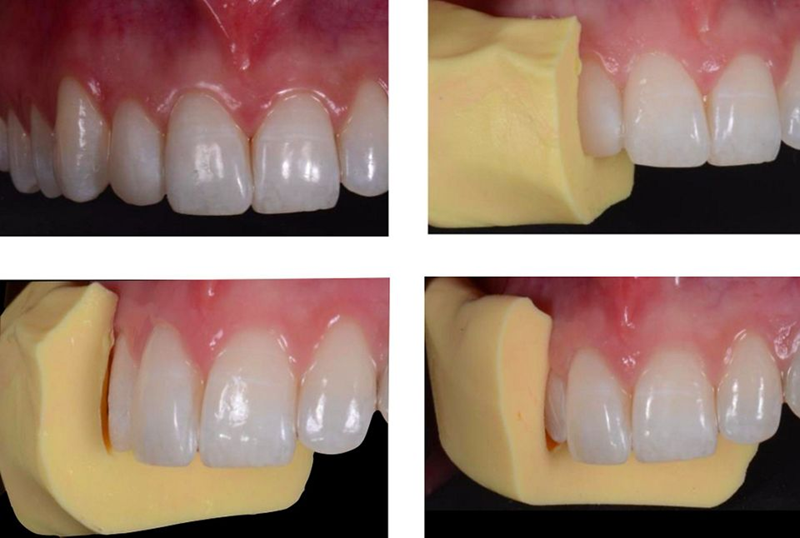

因此,理想的临时牙冠轮廓已为最后的修复阶段做好了准备,包括左侧尖牙的种植体支撑牙冠和右侧侧切牙的陶瓷贴面。为此,使用硅掩模作为指导准备牙齿 12:首先,重新创建初始模型,然后使用硅掩模(在其顶部制作)来验证陶瓷贴面所需的厚度(图47)。

Fig. 47: The lateral incisor was treated with veneer to improve esthetics and avoid ortho treatment. This was an alternative solution offered to patient. As a first step, the mock-up was made once again and a silicon mask, created on top of it and cut in the middle, was used as a guide during the preparation of the tooth. This...

对于陶瓷贴面的粘接,绝对干燥的区域至关重要。因此,用牙坝隔离所有前牙区域并确定预备体的终点线(图57-58)。

Fig. 57: Isolation of the operating field with dental dam for the cementation of the ceramic veneer: for the long-term success of the procedure it is...

Fig. 58: A detail illustrating the finishing line of the preparation: It was perfectly visible and ideal for...